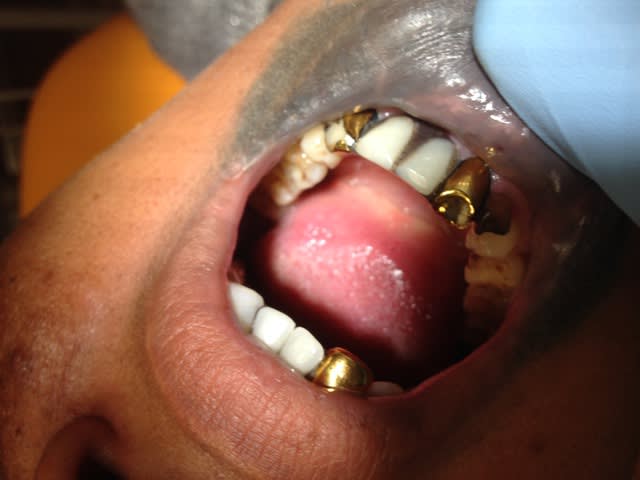

!

Img 0176 pwyr4q - Eugenol

Img 0177 irp4xh - Eugenol

Img 0178 uoinql - Eugenol

Img 0185 ve1nf0 - Eugenol

Et cela perdure depuis 20 ans...Patient CMU, veut changer les dents "jaunes" uniquement, traducteur pour lui expliquer qu'on ne fait pas mieux dans notre beau pays et que cela durera encore 20 ans